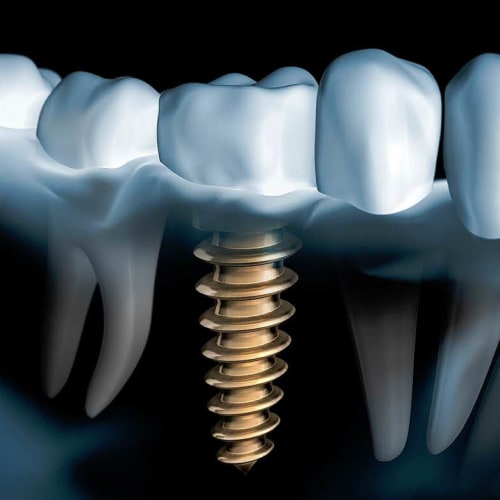

Die Implantologie ist ein Teilgebiet der Oralchirurgie, die sich auf den Ersatz fehlender Zähne durch künstliche Zahnwurzeln, sogenannte Implantate, spezialisiert hat. Implantate bestehen in der Regel aus biokompatiblen Materialien wie Titan und dienen als stabile Basis für den anschliessenden Zahnersatz wie Kronen, Brücken oder Prothesen.

Die Implantologie beinhaltet verschiedene Schritte, von der präzisen Planung und Auswahl des geeigneten Implantats bis hin zur chirurgischen Einbringung in den Kieferknochen und der anschliessenden Versorgung mit dem gewünschten Zahnersatz. Ziel der Implantologie ist es, den Patienten ästhetisch ansprechende und funktionell hochwertige Lösungen zu bieten, die ihren Kaukomfort verbessern und ihre Lebensqualität erhöhen.